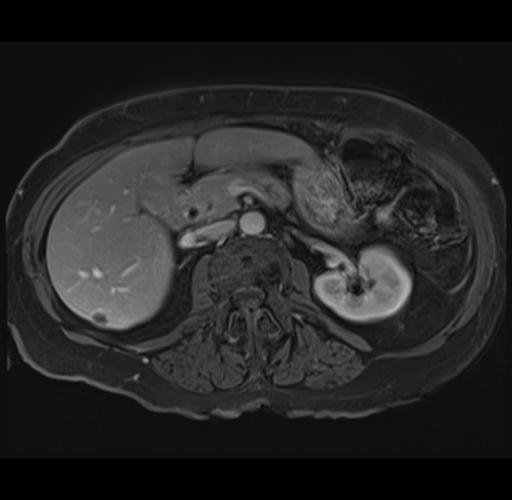

MRI T1